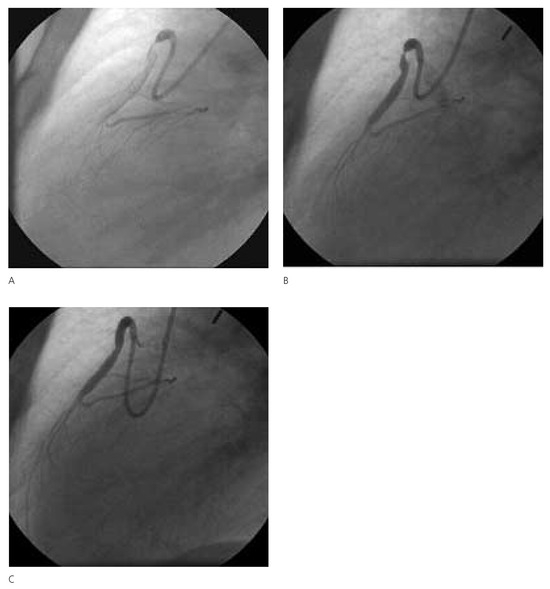

Diabetes leads to both micro- and macrovascular complications. If the major threat to type 2 diabetic patients is ischaemic heart disease, other cardiovascular complications such as heart failure, stroke and lower extremity arterial disease are also...